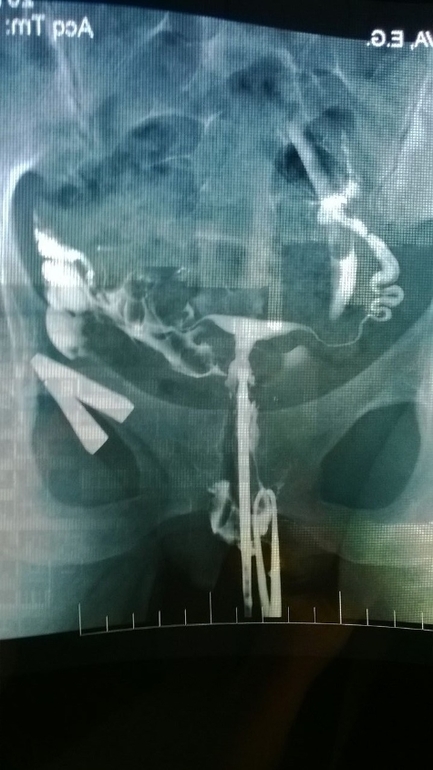

Посмотрите мой снимок ГСГ , плиизз!

Делала ГСГ, врач у меня суровый и не многословный, сделав сказал только что трубы частично проходимы, и не удивительно что вы не беременеете, будем продувать их лекарством. На этом разъяснения закончились.

Выкладываю фото ГСГ и прошу поделиться мнением, кто то что думает? Стоит ли пробовать лекарством или я только потеряю время? И вообще проходимы ли трубы, я в этом снимке ничего не понимаю(((((

справа у вас труба непроходима, я бы не заморачивалась с продуванием , шла бы сразу на лапаро, после нее однозначно будет беременность